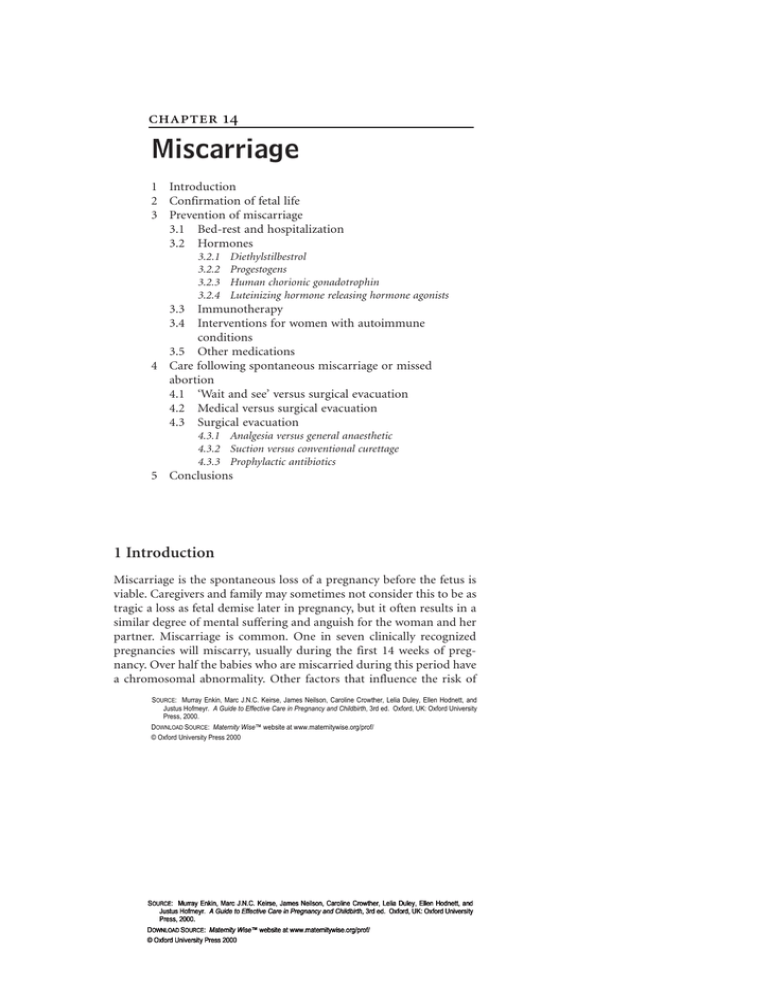

Products & gear. Missed miscarriage is usually diagnosed by ultrasound.

How to tell if you’re having a miscarriage. A lab can examine the tissue to check for signs of a miscarriage. When a miscarriage is confirmed, you'll need to talk to your doctor or midwife about the options.

Miscarriage is commonly diagnosed using a combination of tests, the most standard of which include the hcg blood test, an ultrasound, fetal heart scanning, and a. Passing tissue or blood clots from the vagina. You can practice diaphragmatic breathing at any point after a pregnancy loss, and you don’t even have to get out of bed to do it effectively.